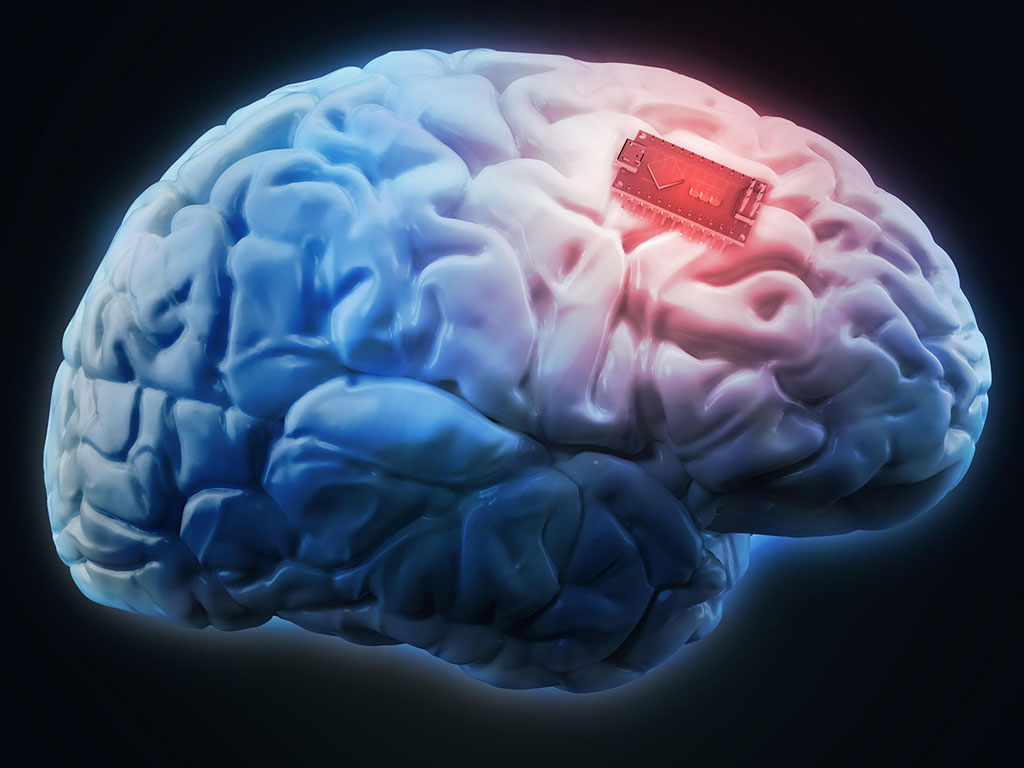

மனித மூளைதான், ஊடுறுவல் மற்றும் தகவல் திருட்டின் அடுத்த கட்ட இலக்காக இருக்கக்கூடும் என இணையப் பாதுகாப்பு நிபுணர்கள் எச்சரிக்கை விடுத்திருக்கிறார்கள். அவர்கள் வெளியிட்டிருக்கும் ஆய்வறிக்கையில், நரம்பு மண்டல பதிய தொழில்நுட்பங்களின் (neural implant technologies) மூலமாக நமது நினைவை வெளிப்படுத்தவோ, இழக்கவோ செய்யக்கூடிய அபாயங்கள் இருப்பதாக எச்சரிக்கை விடுத்துள்ளனர்.

ஏற்கெனவே அடிப்படையான மூளை பதியங்கள் இங்கு இருந்தாலும், தற்போதைய அறிவியல் வளர்ச்சி, நினைவகத்தின் வேதிவினைகளில் நிபுணத்துவம் பெறும் அபாயத்தின் முனைக்கு வந்துவிட்டதைக் காட்டுகிறது.

ஏற்கெனவே அடிப்படையான மூளை பதியங்கள் இங்கு இருந்தாலும், தற்போதைய அறிவியல் வளர்ச்சி, நினைவகத்தின் வேதிவினைகளில் நிபுணத்துவம் பெறும் அபாயத்தின் முனைக்கு வந்துவிட்டதைக் காட்டுகிறது.

அவர்களின் அனுமானப்படி, நினைவக பதியக் கருவிகளை பொருத்தி நினைவை கட்டுப்படுத்தக் கூடிய தொழில்நுட்பம் அடுத்த இருபது ஆண்டுகளில் கிடைத்துவிடும். அமெரிக்க பாதுகாப்புத் துறையின் மேம்பட்ட ஆராய்ச்சி திட்டங்கள் முகமையால் (Defense Advanced Research Projects Agency) நிதியளிக்கப்பட்ட ஆய்வு சமீபத்தில், மூளை குறியாக்க மின் குறியீடுகளை மனிதனிடமிருந்து பிரித்து அவர்களுக்கே திருப்பி அனுப்பச் செய்வதன் மூலம் மூளையின் குறை நேர நினைவு (short-term memory) செயல்திறனை 37 விழுக்காடு வரை அதிகரித்துள்ளது.